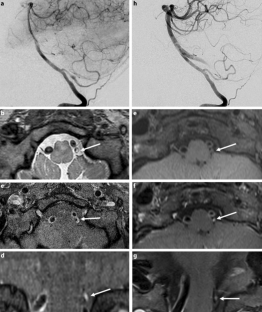

The HR-MRI findings were classified into complete normalization (normal lumen and wall with or without mild enhancement, n = 6), complete normalization with minimal wall changes (focal wall thickening with enhancement but normal luminal angiography, n = 8), incomplete normalization (focal wall thickening with enhancement with dilatation and stenosis on luminal angiography, n = 4), dissecting aneurysm (fusiform aneurysm with residual dissection findings, n = 8) and occlusion (small outer arterial diameter with diffuse contrast enhancement, n = 3).

The use of HR-MRI can demonstrate the distinguishing morphological features of chronic stage of spontaneous and unruptured ICAD as complete normalization, complete normalization with minimal wall changes, incomplete normalization, dissecting aneurysm and occlusion.